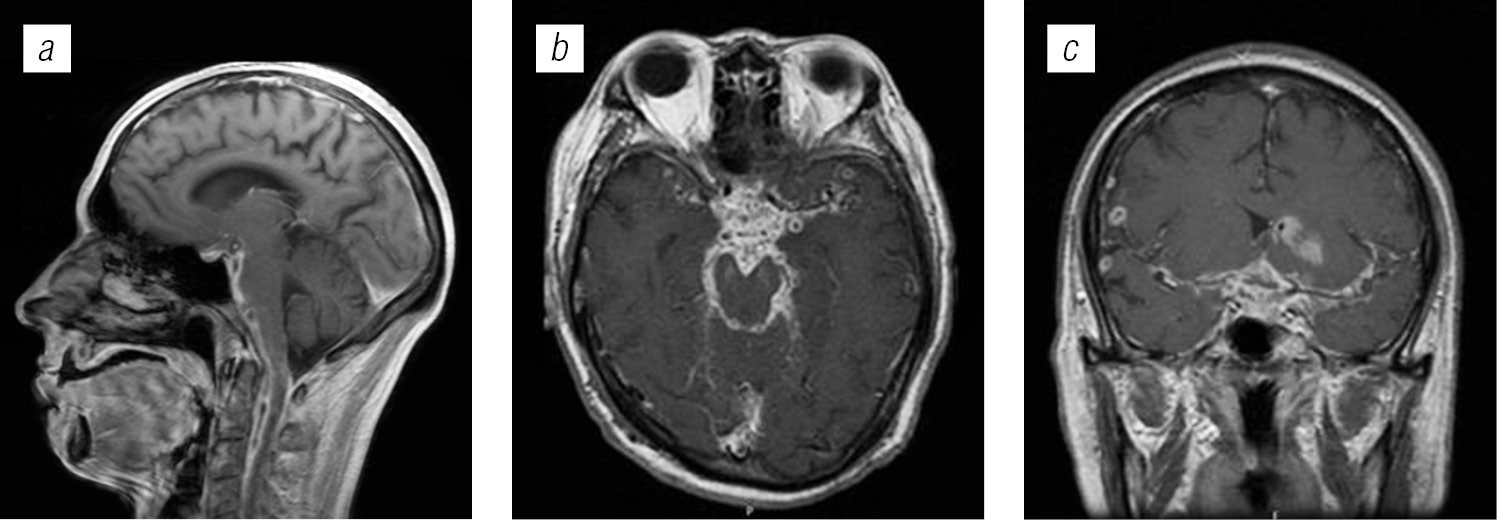

Заключение. Для правильной расшифровки природы поражения головного мозга необходимо использовать комплексные исследования, в том числе клинико-лабораторные и лучевые методы. Магнитно-резонансная томография с внутривенным контрастированием является методом выбора при обследовании головного мозга у ВИЧ-инфицированных пациентов.

Структура поражения головного мозга у ВИЧ-инфицированных больных имела различную природу: в 54,4 % случаев обнаружены признаки оппортунистических и вторичных заболеваний, в 24,9 % — признаки ВИЧ-энцефалопатии, в 13,2 % — признаки неспецифических изменений мелких сосудов головного мозга, указывающие на преждевременное старение или аномалию развития; в 7,56 % признаки вовлечения головного мозга в патологический процесс не выявлены.

Структура оппортунистических и вторичных заболеваний была представлена токсоплазмозом головного мозга (18,3 %), герпесвирусными поражениями (12,2 %), прогрессирующей мультифокальной лейкоэнцефалопатией (10,24 %), нейроинфекцией неуточненной этиологии (12,2 %), криптококкозом (4,39 %), туберкулезом (2,44 %), лимфомой головного мозга (2,44 %), МАК-инфекцией (0,24 %).